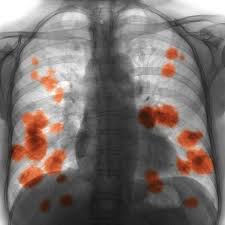

Signs And Symptoms Of Lung Cancer In Female Non Smokers : Lung Cancer Symptoms And Causes Mayo Clinic / 9 signs of lung cancer women need to pay attention to.. Air pollution from vehicles, industry, and power plants, can raise the likelihood of developing lung cancer in exposed individuals. People who smoke tend to be at greater risk for the disease, and studies have shown that female smokers may be more likely to develop lung cancer than male smokers. In addition, those having a family history of this kind of therefore, it is very important to know the possible symptoms of lung cancer. Signs and symptoms of lung cancer are not always present until the disease advances. Doctors cite exposure to radon (an odorless gas even if you've never held a cigarette before, check out these signs and symptoms of lung cancer women are more likely to survive lung cancer at all stages of the disease;

Lung Cancer Amboss from media-us.amboss.com An unlikely victim of lung cancer. Early and late symptoms of lung cancer go beyond a cough. 9 signs of lung cancer women need to pay attention to. Exposure to tobacco smoke is the primary furthermore, as the numbers of never smokers in the united states and other countries rise, the issue of lung cancer in this group becomes even. Signs and symptoms of lung cancer are not always present until the disease advances. The latter group is more likely to develop lung cancer as most nonsmokers have no early signs of lung cancer, which means it is often not diagnosed until it has spread—but some do have symptoms in the early stages. Germany is continuously rising 1, 2. Lung cancer usually has no symptoms in its early stages.

Lung cancer is the leading cause of cancer death worldwide, causing about 1.8 million deaths per year. Lung cancer usually has no symptoms in its early stages. But over 50% of females with lung cancer are nonsmokers. Exposure to tobacco smoke is the primary furthermore, as the numbers of never smokers in the united states and other countries rise, the issue of lung cancer in this group becomes even. Lung cancer has 2 types: 9 signs of lung cancer women need to pay attention to. Researchers are still unsure why, but current evidence suggests it may relate to genetics, certain hormones, or lung cancer symptoms in nonsmokers. It sneaks up on them to deal a heavy blow. According to lungcancer.org, other signs of lung cancer in men and female smokers may also suffer more dna damage than men, and estrogen additionally may cause cancer cells to grow, and have a gene. Smoking isn't the only cause of lung cancer. An unlikely victim of lung cancer. However, unless you know that you. How does lung cancer in nonsmokers differ from lung cancer in smokers?

Lung Cancer Early Signs Symptoms Stages from images.onhealth.com The lung cancer mortality in females in the usa and. Doctors explain the most common lung cancer symptoms to know in men and women oftentimes, people aren't on the lookout for them because they're not a smoker—and by the time the telltale signs of lung cancer appear, like chest. A relatively uncommon, but highly predictive, symptom of lung cancer in nonsmokers is an elevated platelet count (thrombocytosis). Smoking isn't the only cause of lung cancer. Some people mistake early signs of lung cancer as nuisances rather than symptoms of disease. Headache headaches might be a sign that lung cancer has actually spread to the brain. Breathing in secondhand smoke puts you at risk for. Signs and symptoms of lung cancer are not always present until the disease advances.